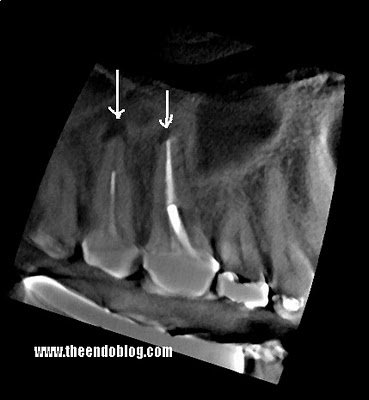

An additional slice through the palatal roots shows that #2 also has a significant periapical lesion requiring treatment.

A sagittal view of #2 again shows the extent of the lesion.